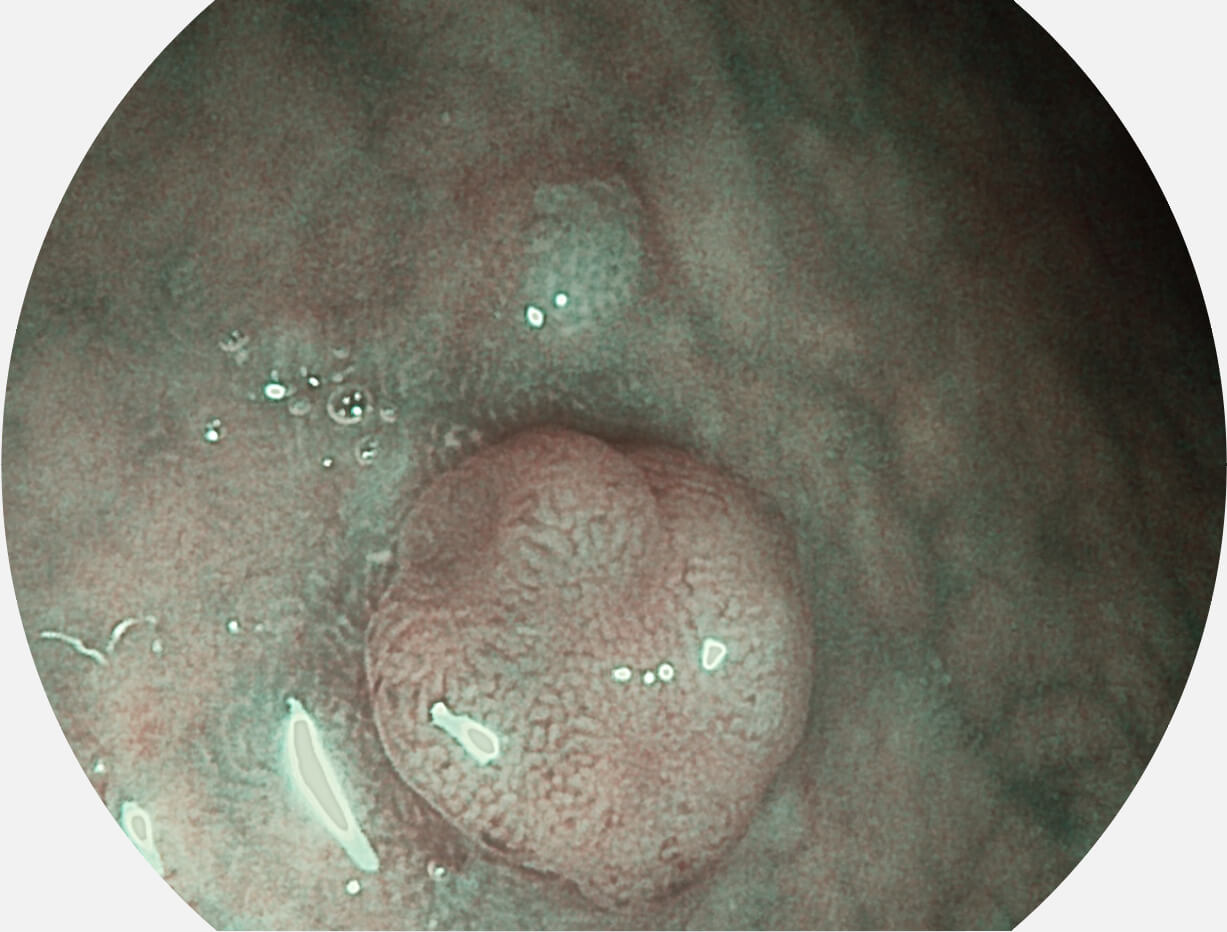

图像具有高亮度、高黏膜血管颜色对比度的特点,且不改变粘液、食物残渣、粪便的基本颜色,可在中远景下进行观察,助力消化道早期疾病的诊断。

强调浅层黏膜结构的同时,保证照明亮度和提升浅层微血管与中层血管颜色对比度,病变边界更清晰。